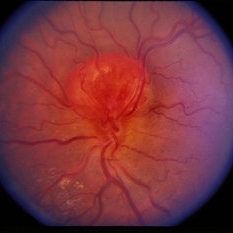

Retinal Capillary Hemangioblastoma

Feb 20 2015 by H. Michael Lambert, MD

Optic nerve in this eye with fibrosis over the nerve and posterior pole.

Condition/keywords: retinal capillary hemangioblastoma